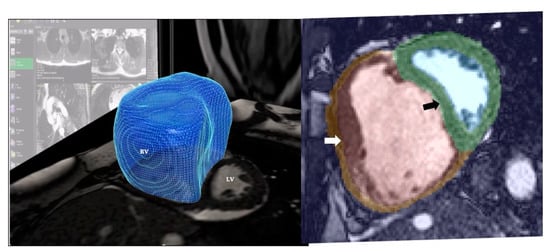

- Avendi, M.R.; Kheradvar, A.; Jafarkhani, H. Automatic Segmentation of the Right Ventricle from Cardiac MRI Using a Learning-Based Approach: Automatic Segmentation Using a Learning-Based Approach. Magn. Reson. Med. 2017, 78, 2439–2448. [Google Scholar] [CrossRef]

- Bai, W.; Shi, W.; de Marvao, A.; Dawes, T.J.W.; O’Regan, D.P.; Cook, S.A.; Rueckert, D. A Bi-Ventricular Cardiac Atlas Built from 1000+ High Resolution MR Images of Healthy Subjects and an Analysis of Shape and Motion. Med. Image Anal. 2015, 26, 133–145. [Google Scholar] [CrossRef]

- Mauger, C.; Gilbert, K.; Lee, A.M.; Sanghvi, M.M.; Aung, N.; Fung, K.; Carapella, V.; Piechnik, S.K.; Neubauer, S.; Petersen, S.E.; et al. Right Ventricular Shape and Function: Cardiovascular Magnetic Resonance Reference Morphology and Biventricular Risk Factor Morphometrics in UK Biobank. J. Cardiovasc. Magn. Reson. 2019, 21, 41. [Google Scholar] [CrossRef]

- Swift, A.J.; Lu, H.; Uthoff, J.; Garg, P.; Cogliano, M.; Taylor, J.; Metherall, P.; Zhou, S.; Johns, C.S.; Alabed, S.; et al. A Machine Learning Cardiac Magnetic Resonance Approach to Extract Disease Features and Automate Pulmonary Arterial Hypertension Diagnosis. Eur. Heart J.—Cardiovasc. Imaging 2020, jeaa001. [Google Scholar] [CrossRef]

- Dawes, T.J.W.; de Marvao, A.; Shi, W.; Fletcher, T.; Watson, G.M.J.; Wharton, J.; Rhodes, C.J.; Howard, L.S.G.E.; Gibbs, J.S.R.; Rueckert, D.; et al. Machine Learning of Three-Dimensional Right Ventricular Motion Enables Outcome Prediction in Pulmonary Hypertension: A Cardiac MR Imaging Study. Radiology 2017, 283, 381–390. [Google Scholar] [CrossRef]